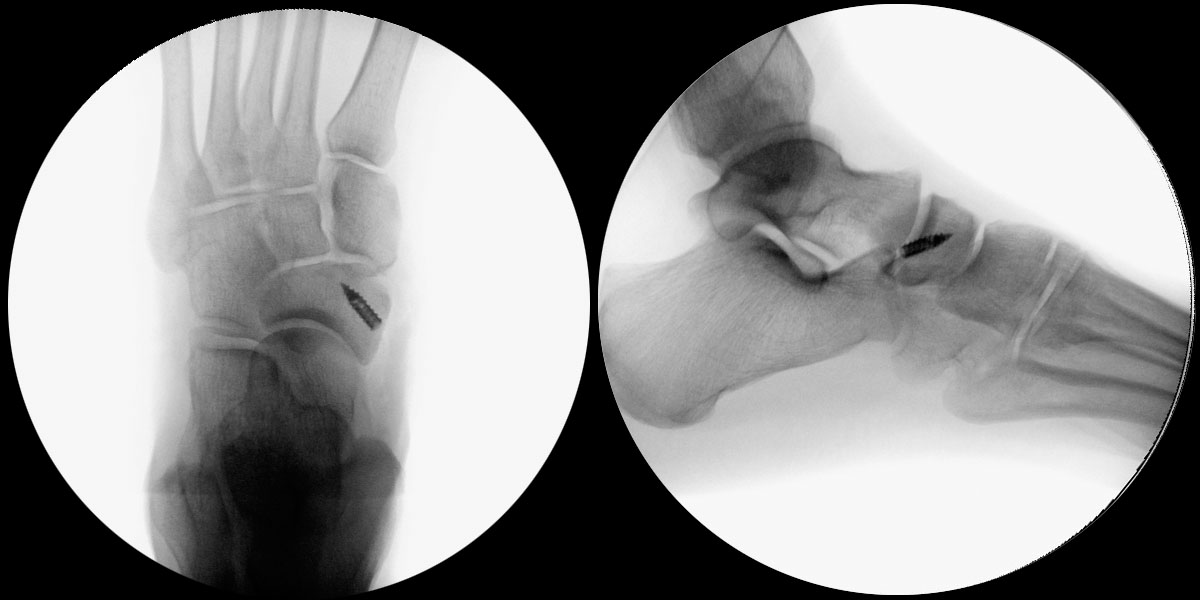

- Intra- und postoperativ Röntgenkontrolle Fuß in 2 Ebenen zur Dokumentation. Operational zusätzliche 3 Ebene in 45° Supination.

- Intraoperativ iatrogene Osteotomie des Os naviculare außerhalb des Synchondrosen-Spaltes bei Mobilisation des Os tibiale externum. Hier ist die exakte Lage des Synchondrose-Spaltes unter Bildverstärker zu finden und zu dokumentieren, bevor der Spalt mit Meißel mobilisiert wird.

- Fehllage des Knochenankers. Die korrekte Platzierung des Knochenankers wird unter Bildverstärker in 2 Ebenen kontrolliert und dokumentiert.